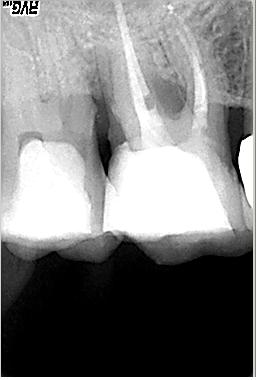

Zustand unmittelbar vor Behandlungsbeginn im Juni 2003. Die Fraktur des distalen Zahnanteils hat die Patientin jetzt zur Einwilligung in die Behandlung motiviert. Auffällig ist in dieser Projektion die besonders starke Krümmung der mb Wurzel sowie die knochennahe Defektlage distal. Es erfolgte zunächst die Kariesentfernung gefolgt von einer chirurgischen Kronenverlängerung zur Herstellung der biologischen Breite sowie Ermöglichung des sog. Ferrule-Effektes. Danach wurde der Zahn adhäsiv aufgebaut. Erst jetzt wurde mit der eigentlichen WKB begonnen

Röntgenmeßaufnahme

Röntgenmeßaufnahme nach vorgängig durchgeführter endometrischer Längenbestimmung